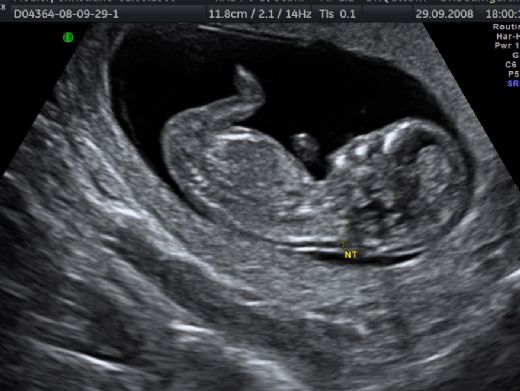

Bu belirtiler, kesin bir tanı koymak için yeterli değildir; fakat risk faktörlerinin belirlenmesi, daha ileri testler yapılmasını teşvik edebilir. Tanı Yöntemleri Hamilelikte Down sendromunun tanısı için çeşitli testler mevcuttur. Bu testler, genellikle ilk ve ikinci trimesterde yapılır:

Bu testlerin her biri, Down sendromu riskini değerlendirmek için kullanılabilir, ancak kesin tanı için genetik testler gereklidir. Hamilelikte Down Sendromu Tedavisi Down sendromunun tedavisi, doğrudan hamilelik döneminde değil, doğumdan sonra başlar. Ancak, hamilelik öncesinde ve sırasında bazı önleyici adımlar atılabilir: